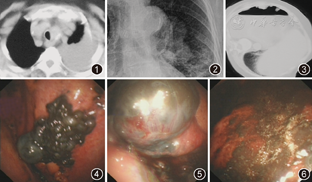

患者女,78岁,主因"气短1年,加重伴胸痛2周"于2011年12月12日入院。病例特点为1年前无诱因出现气短,无明显其他伴随症状,未引起重视。入院前2周因气短加重,伴胸痛、咳嗽及少许白痰,于外院门诊行胸部CT检查提示左肺下叶支气管形态改变,左侧胸膜增厚并软组织肿块形成,左侧胸膜腔少量积液,左肺炎并部分肺不张,行支气管镜检查及X线胸片示:左肺门球形高密度影,边界清晰(图1,图2)。曾于外院行气管镜见镜下未报明显异常,于左下叶背段支气管盲检回报慢性炎症。患者入院前13 d行支气管镜检查发现隆突上5 cm处气管环左侧壁呈外压性改变,长约3 cm,左肺下叶背段外压性改变,于该处盲检病理结果示支气管黏膜-肺组织慢性炎伴间质纤维组织增生,部分肺泡上皮增生活跃。为进一步治疗收入院。发病后无发热、咯血等症,无皮肤黑痣突然增大、瘙痒及渗液。既往有高血压病史2年。体格检查:营养中等,无明显消耗貌,全身皮肤光滑、弹性好,未见黑痣异常改变。全身浅表淋巴结未触及肿大,口唇无发绀,气管无明显移位。左侧呼吸动度减弱、左下肺语颤减弱,左肺背部第8肋下叩诊浊音,呼吸音减低,左肺可闻及少许细小湿性啰音,呼吸音粗糙,双肺未闻及干鸣音。心率86次/min,律齐,各瓣膜听诊区未闻及杂音。腹软,肝、脾肋下未触及,移动性浊音阴性。四肢活动不受限,无杵状指。辅助检查:血常规:白细胞计数5.91×109/L,中性粒细胞为0.56,血红蛋白125 g/L。肝功能检查总蛋白含量为57.4 g/L,白蛋白为34.8 g/L,肾功能、电解质水平及凝血功能等其余实验室检查结果未见明显异常。肺部肿瘤标志物:癌胚抗原(CEA)1.05 ng/ml、铁蛋白含量173.20 μg/L、特异性烯醇化酶(NSE)21.74 ng/ml、CA125 136.1 U/ml、CA21-1 0.85 ng/ml。胸腔穿刺1次为血性胸腔积液,胸腔积液生物化学检查:氯化物101.0 mmol/L、总蛋白44.7 g/L、葡萄糖6.84 mmol/L、乳酸脱氢酶403 U/L、腺苷脱氨酶5.00 U/L。胸腔积液常规:血性浑浊、浆液黏蛋白定性阳性、白细胞计数1.47×109/L、细胞总数130×109/L。胸腔积液病理细胞学检查未查见癌细胞。腹部B超及肾上腺探查未见异常、头颅CT未见异常、心脏彩色多普勒超声未见异常。于12月13日建立人工气胸,人工气胸建立后行胸部CT检查示:胸膜增厚并软组织肿块影(图3)。后进行胸腔镜检查:镜下见下胸壁呈广泛的黑色素沉积样改变,膈顶、叶间裂及肺表面、壁层胸膜多发的孤立或融合的黑色素瘤样增生改变(图4,图5,图6),较大者直径约4 cm,于不同部位取活检共10块,活检时组织松软,伴有少许出血,出血总量约5 ml,局部喷洒蛇毒血凝酶1 U,观察后再未见明显活动性出血,胸腔镜检查后行胸腔闭式引流术等待病理检查结果。病理组织检查行免疫组织化学后诊断恶性黑色素瘤,免疫组织化学结果显示HMD45、S-100蛋白及黑色素瘤-PAN染色均阳性、多巴胺染色呈绿色阳性,含铁血黄素染色阴性。考虑到患者年龄及一般情况较差,给予局部注入顺铂20 mg及A群链球菌封闭胸膜腔治疗,未行全身治疗出院。

黑色素瘤是一种起源于黑色素细胞的恶性肿瘤,由外胚层神经嵴细胞分化而来,广泛存在于全身皮肤的表皮,具有致死率高、易转移的特点。黑色素瘤以鼻腔、肛管直肠及口腔为好发部位,发生于黏膜者少见[1]。对274例黑色素瘤的病例回顾分析发现,以下肢(包括髋、足)、上肢(包括肩)、直肠、眼及躯干部位恶性黑色素瘤最为多见[2],而胸膜恶性黑色素瘤因临床罕见,目前尚无其发病率的报道,基本上均以个案报道形式出现[3,4]。诊断方式包括:胸膜穿刺活检、胸腔积液瘤细胞、开胸活检或根据既往病史诊断等。胸膜恶性黑色素瘤无论是临床表现还是影像学检查均不典型,病理学特征亦不典型,单纯病理细胞学检查极易漏诊或误诊,本例胸腔积液细胞学检查阴性。本例气短时间1年,但因症状不严重,未引起重视,此次病情加重仅2周,胸部CT示左侧胸膜腔少量积液,胸膜增厚,肺内似可见软组织肿块,考虑肺癌胸膜转移,但2次支气管镜检,镜下均未见异常。入院后胸部穿刺1次,病理细胞学未见异常,胸腔积液生化及常规呈渗出液表现,为尽快使患者得到确诊,我们进行了内科电子胸腔镜检查,检查中发现,患者胸部CT显示的软组织肿块实际上位于叶间裂,为脏层胸膜的瘤性改变,而非肺内病灶,与支气管镜下外压性改变相符。且在胸腔镜下可直视观察到患者壁、脏层胸膜上的新生物形态,无论从形态学还是从外观上均呈现典型黑色素瘤的改变,就像胸膜上长的痣。因而镜下诊断高度怀疑胸膜黑色素瘤,后来病理组织学检查及免疫组织化学结果也证实了这一疾病。本例患者之所以能够快速确诊,依赖了内科电子胸腔镜这一简便、可行、创伤性小的检查方法,不仅可以在直视下进行多点活检,获取病理组织学检查结果,并可以从镜下病灶的表现形态上对病灶的性质进行初步判断。